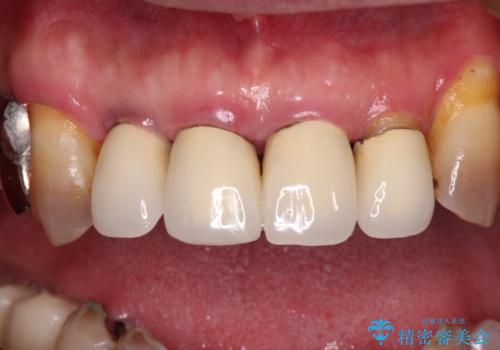

- 奥歯が咬みにくく、前歯がぐらぐらするとのことで来院された患者様です。

咬合力が強く、奥歯が欠損している状態でした。

欠損部はインプラントによる補綴治療を行うこととし、臼歯部が安定した後に、上下前歯部をオールセラミッククラウンにて補綴治療を行うこととしました。

上顎前歯に歯周ポケットの深い部分がありましたが、インプラントの仮歯で奥歯がしっかりと噛めるようになると、1年程度で深い歯周ポケットは解消されました。

前歯部の審美面も大幅に改善され、大変満足していただけました。